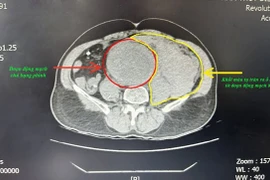

Động mạch chủ là động mạch lớn nhất trong cơ thể dẫn máu có chứa nhiều oxy được bơm ra từ tim hoặc đưa máu đi xa khỏi tim. Động mạch chủ bụng cung cấp máu cho phần dưới cơ thể. Nếu túi phình động mạch vỡ có thể khiến bệnh nhân tử vong trong vòng vài phút.